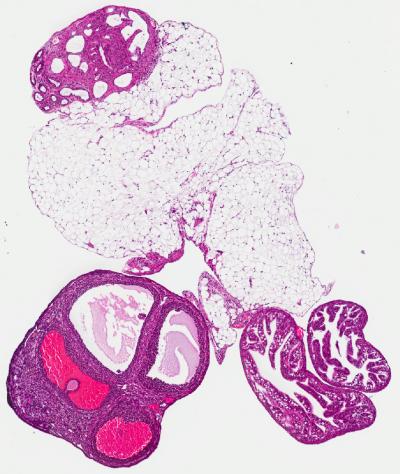

PROVIDENCE, R.I. [Brown University] — In the complex genomic and molecular conspiracy that gives rise to ovarian cancer, what if researchers have been missing a whole set of suspects because they've been hiding in plain sight? That's the argument made by Brown University biologists in a new paper that combines evidence from original research and prior studies to raise new suspicions about a set of proteins that assist in regulating gene expression.

Scientists need such new leads in their investigation of ovarian cancer, the most deadly reproductive cancer. Mortality has remained tragically steady since the last major therapeutic breakthrough came in the 1990s. Pursuing the evidence that these proteins may be involved could allow researchers to make new progress.